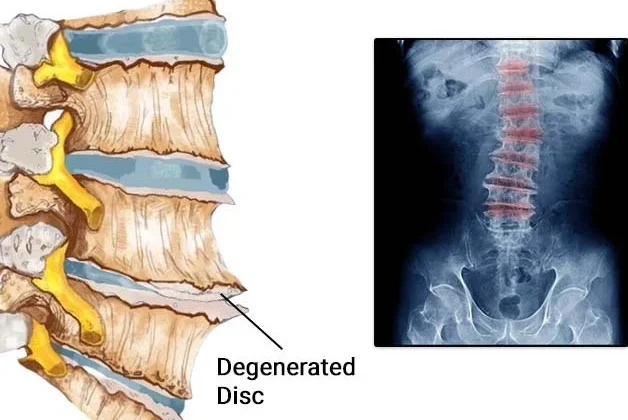

كيف تؤثر الانحناءات غير الطبيعية على الغضاريف؟

بين كل فقرتين من فقرات العمود الفقري توجد غضاريف (أقراص فقرية) تعمل كممتصات للصدمات وتُسهم في مرونة الحركة. عندما يحدث انحناء في العمود، يتوزع الضغط بشكل غير متساوٍ على هذه الأقراص، مما يؤدي إلى:

تآكل الغضاريف بشكل أسرع.

تقليل قدرتها على امتصاص الصدمات.

زيادة خطر الإصابة بالانزلاق الغضروفي أو تأكل الغضاريف.

ما العلاقة بين اعوجاج العمود الفقري والانزلاق الغضروفي؟

تشير الدراسات إلى أن المرضى الذين يعانون من الجنف، خاصةً الحالات المتوسطة إلى الشديدة، معرضون بنسبة أكبر للإصابة بـ:

الانزلاق الغضروفي: حيث تتحرك نواة القرص وتضغط على الأعصاب.

الرنين المغناطيسي (MRI): لتحديد وجود انزلاق غضروفي أو تآكل في الأقراص.